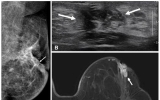

[나이스데이] 국내 연구진이 수술 전 MRI(자기공명영상)가 50세 이하 유방암 환자의 재발 예방에 효과적이라는 사실을 규명했다. 특히 예후가 나쁘고 재발률이 높은 '호르몬 수용체 음성 유방암'은 재발 위험이 60% 이상 낮아지는 것으로 나타났다. 이는 젊은 유방암 환자의 맞춤형 치료 가능성을 높이고, 유방 MRI 기반의 정교한 치료 계획을 수립하는 중요한 가이드라인이 될 것으로 기대된다. 서울대병원은 하수민·연희라 영상의학과 교수, 김홍규 유방내분비외과 교수팀이 2011년부터 2017년까지 수술을 받은 50세 미만…